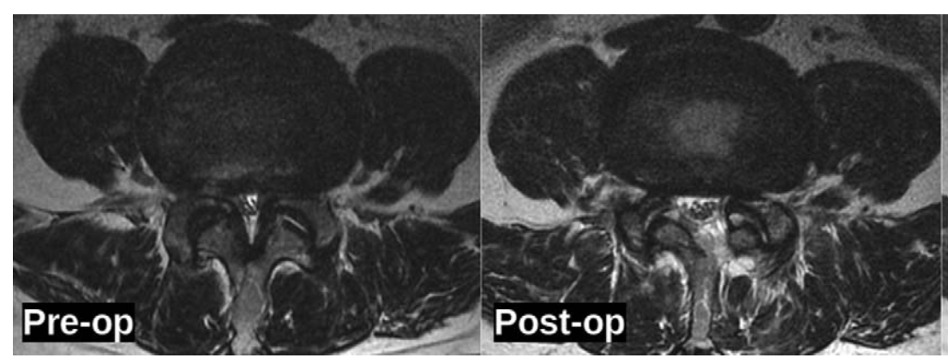

Table 3 presents the radiologic outcomes observed in patients undergoing full-endoscopic decompression for lumbar spinal stenosis. A significant increase in the canal cross-sectional area was noted postoperatively, with a mean area of 155.2 ± 32.2 mm² compared to the preoperative measurement of 75.78 ± 28.45 mm² (p <0.01). In terms of the intervertebral height index (IHI), preoperative values were recorded at 30.87 ± 5.49%, which slightly decreased to 30.28 ± 5.21% postoperatively; however, this change was not statistically significant (p >0.05). Regarding segmental angulation, measurements were obtained for both extension and flexion angles, with extension averaging 7.01° ± 1.74° and flexion measuring 6.51° ± 1.56°. Range of motion (ROM) was assessed, demonstrating a mean extension of 2.87 ± 0.53 mm and a flexion of 2.78 ± 0.54 mm. Facet joint dimensions were evaluated bilaterally, revealing a slight reduction in ipsilateral facet length from 14.8 ± 0.9 mm preoperatively to 14.4 ± 0.7 mm postoperatively, and minimal change in contralateral facet length from 14.9 ± 0.6 mm to 14.8 ± 0.6 mm. Neither change reached statistical significance (p >0.05), indicating that the surgical technique preserved facet joint integrity. Lastly, the Pfirrmann classification system indicated no change in disc degeneration status.

Radiologically, our study observed a significant increase in the canal cross-sectional area, which improved from 75.78 mm² preoperatively to 155.2 mm² postoperatively. This is consistent with findings from previous studies,10,15 which also reported substantial increases in canal cross-sectional area following decompression surgeries, emphasizing the efficacy of the surgical intervention in alleviating spinal canal obstruction.

The >100% expansion in canal dimensions directly correlates with our clinical outcomes, as the achieved 155.2 mm² far exceeds the 100-130 mm² threshold considered necessary for symptomatic relief in lumbar stenosis. Importantly, the preserved facet joint dimensions (pre-op: 14.8±0.9mm vs post-op: 14.4±0.7mm, p>0.05) demonstrate our technique’s ability to maintain spinal stability while achieving adequate decompression, a distinct advantage over conventional laminectomy where facet integrity is often compromised.